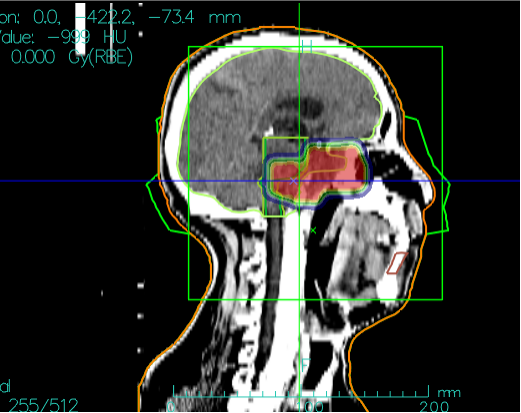

Carbon Ion Treatment Plan Dose Cloud Chart, Perfectly Protecting the Brainstem

Due to the special location of skull base chordomas, they often invade and compress the brainstem. Auntie Qiao's lesion protruded into the pons. Conventional photon radiotherapy and similar methods cannot protect the brainstem, whereas heavy ions have unique physical advantages enabling precise "targeting" of the tumor. The biological advantages of heavy ions have a good effect on radiation-resistant tumors like chordomas. Auntie Qiao's skull base chordoma with brainstem compression has been "cured."